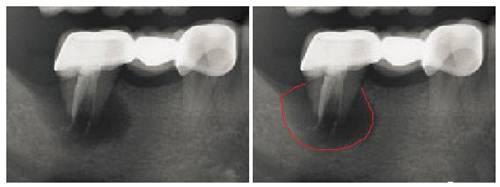

拍X光片才能发现智齿牙根已经侵入下颌神经

贸然拔除智齿可能造成神经的损伤!!!